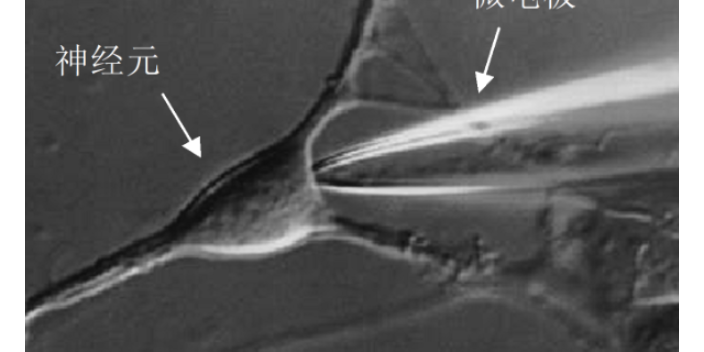

上海藥理學膜片鉗成像應用 歡迎咨詢 上海司鼎生物科技供應

上海司鼎生物科技有限公司